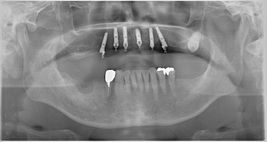

一日も歯がないという状態はありません。 この写真の方も前歯しか残っていませんが、インプラント手術当日まで前歯は残しておいて、その当日に抜歯、インプラントを入れて仮歯を固定しています。つまり、歯は一日で入るので、歯が無い、見た目が悪いという状態は全くありませんので、ご心配なく。大分県大分市スマイルライン歯科ではオールオンフォー(all- on- 4)の治療を全国でもいち早く行い数多くの症例を手掛けてきました。そして治療を行ったすべての患者様に喜んで頂いておりますのでご希望の方はまず、CTレントゲンなどで骨の形を診査しますのでお問い合わせください。

先日行ったall on 4の症例の写真です